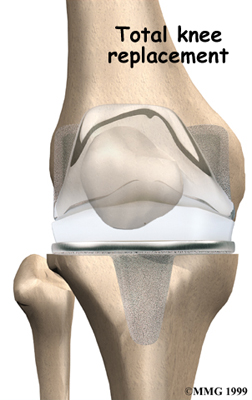

Artificial Knee Replacement

An artificial knee replacement is the ultimate solution for advanced knee OA.

Surgeons prefer not to put a new knee joint in patients younger than 60. This is because younger patients are generally more active and might put too much stress on the joint, causing it to loosen or even crack. A revision surgery to replace a damaged prosthesis is harder to do, has more possible complications, and is usually less successful than a first-time joint replacement surgery.

Related Document: FYZICAL's Guide to Artificial Joint Replacement of the Knee